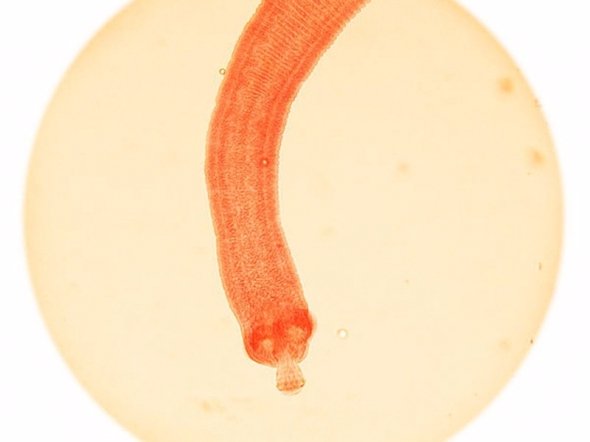

Аскариди - 4500 смертей на рік

Аскариди викликають хворобу під назвою аскоріаз, яка щорічно вбиває приблизно 4500 осіб. ВООЗ зазначає, що зараження відбувається в тонкому кишечнику людей і це захворювання більше вражає дітей, ніж дорослих.